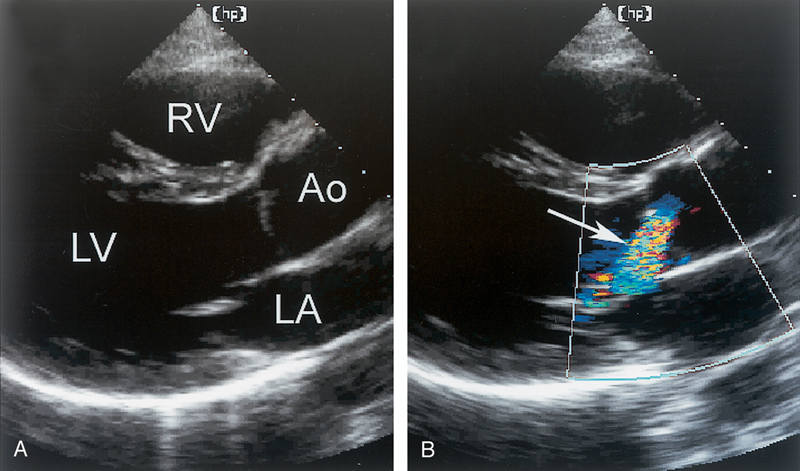

فحوصات تشخيصية لبعض امراض القلب والشرايين التاجية